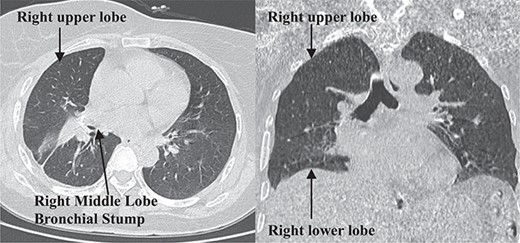

The patient was admitted on 20 March 2024. Enhanced chest CT revealed a solitary cystic lung lesion in the right middle lobe, measuring 8.0 cm × 7.3 cm, with a thin wall and slight compression of the right cardiac border (Fig. 1).

The enhanced scan displayed mild enhancement of the cyst wall without abnormal blood vessels. Pulmonary function tests indicated mild obstructive ventilatory impairment. The patient could ascend 13 floors without stopping during a stair-climbing test. Given the large size of the cyst and a decade of recurrent cough despite conservative treatment, the patient chose surgical intervention. After multidisciplinary consultations, a thoracoscopic right middle lobectomy was planned [7, 8].

A follow-up chest CT scan 1-month post-surgery showed no pneumothorax, pleural effusion, or pneumonia (Fig. 4). The patient reported no symptoms of cough, sputum production, chest tightness, or shortness of breath and exhibited good daily activity performance.

Postoperative 1-month follow-up non-contrast chest computed tomography.